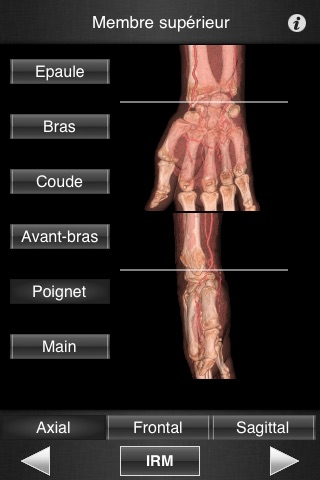

Il contient 502 coupes d’IRM jointives (2-4 mm dépaisseur) dans les trois plans de l’espace.

- Défilement fluide des images dans les trois plans de l’espace.

- Repérage précis du niveau de coupe grâce aux images 3D (Volume Rendering)